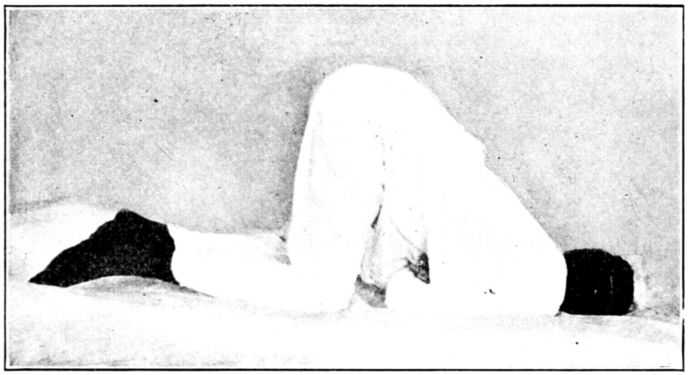

| 129, 130, 131, 132, 133, 134, 135. | Bed exercises taken during the puerperium | 350 to 353 |